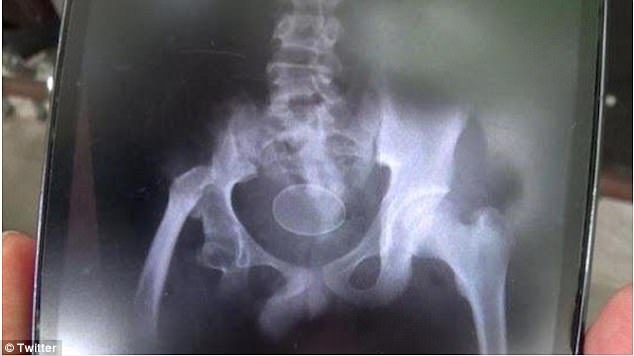

වෛද්යවරුන් විසින් මෙය නිරීක්ෂණය කිරීමට එක්ස්රේ පරීක්ෂණයක්ද සිදුකර තිබෙනවා.

එහිදී දක්නට ලැබී තිබෙන්නේ බිත්තර පවතින බවයි.